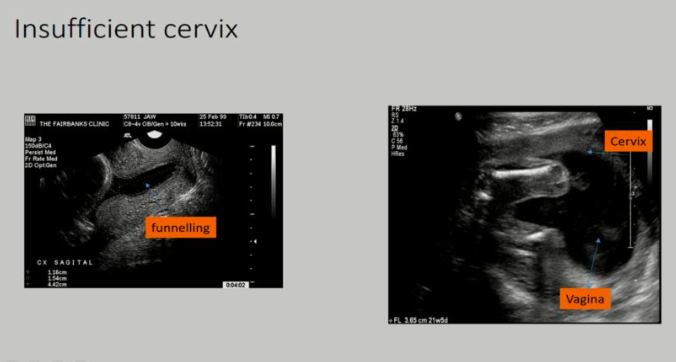

Describe how an insufficient cervix might affect pregnancy

Insufficient cervices usually cause a painless, premature dilation resulting in early birth, most commonly in the second trimester before fetal life is viable

How could insuffient cervices be treated/managed in subsequent pregnancies?

the placement of a cerlage